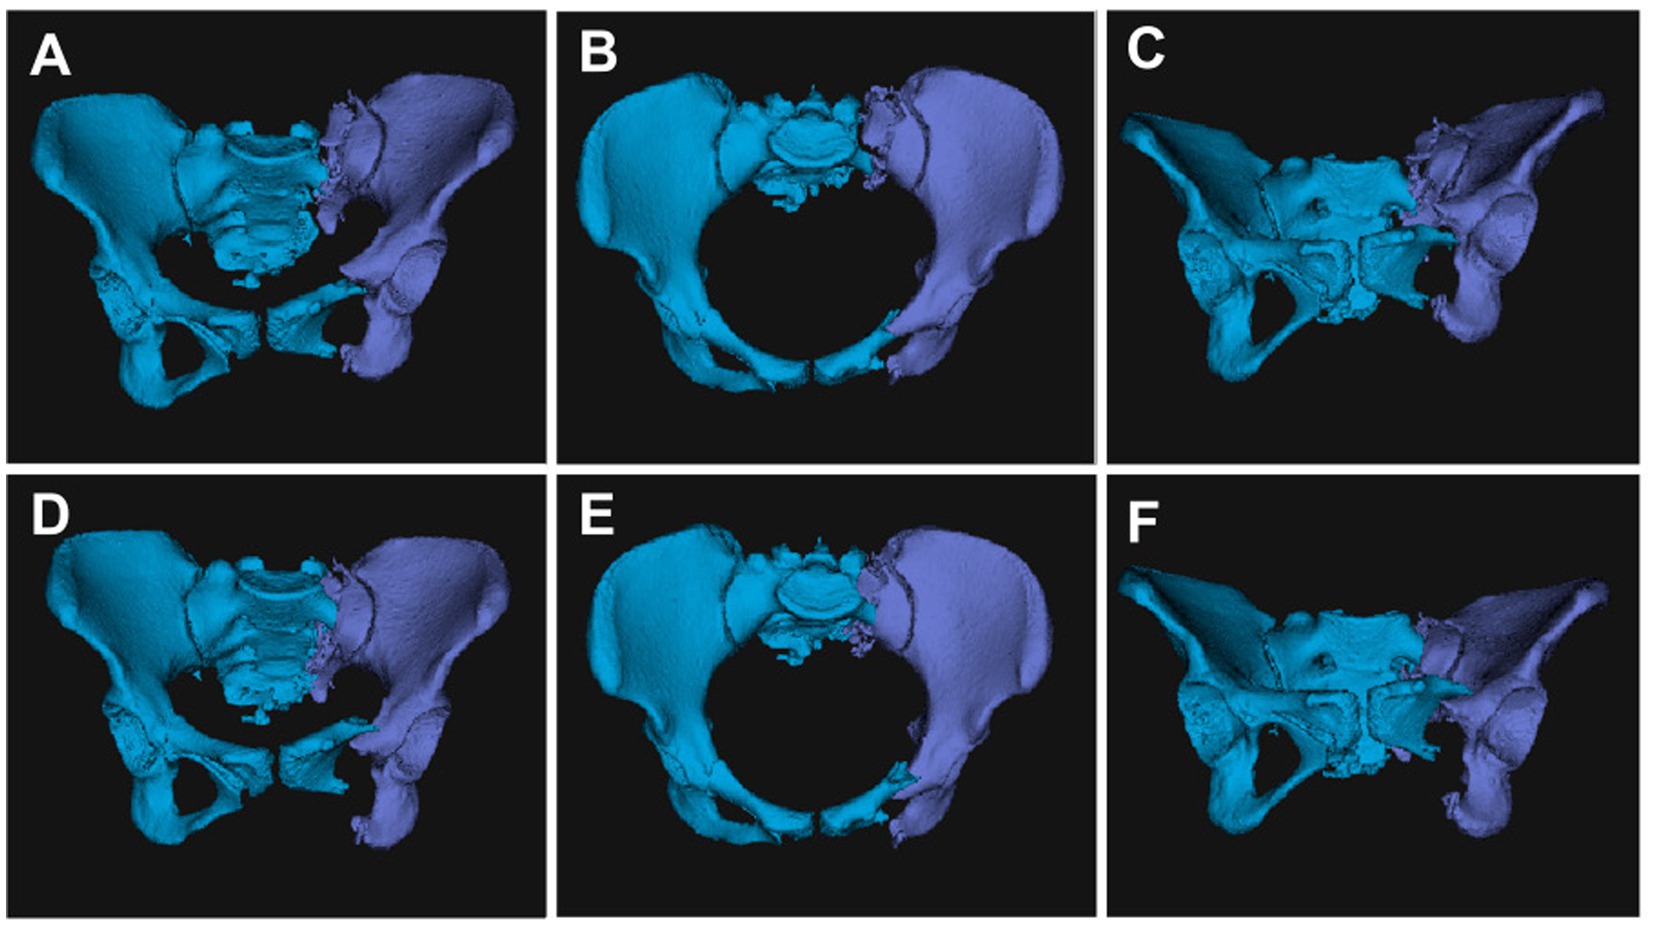

3.4 Internal fixation model design

In this study, standard sacroiliac screws are defined as screws that traverse the fracture line and reach the midline of the sacrum. Extended sacroiliac screws are defined as screws that traverse the fracture line and pass through the contralateral ilium. Three internal fixation models were established, as shown in Figures 2A–C: (1) S1 standard sacroiliac screw + S2 extended sacroiliac screw (SDS1EDS2); (2) unilateral L5 segment iliac-lumbar fixation + S1 standard sacroiliac screw (L5SDS1); (3) unilateral L5 segment iliac-lumbar fixation + S2 extended sacroiliac screw (L5EDS2). The lengths and diameters of the lumbar pedicle screws and iliac screws were 45 mm and 6.5 mm, and 70 mm and 7.5 mm, respectively, while the diameter of the sacroiliac screw was 7.3 mm. All materials are made of titanium alloy. A Boolean operation was performed on the three fixation models, and the vertical displacement of each model was recorded.

Figure 2

(A) SI standard sacroiliac screw + S2 extended sacroiliac screw (SDS 1 EDS2). (B) Unilateral segment iliac-lumbar fixation + SI standard sacroiliac screw (L5SDS1). (C) Unilateral 1.5 segment iliac-lumbar fixation + S2 extended sacroiliac screw (L5EDS2). (D) Maximum von Mises stress contour map of SDSIEDS2. (E) Maximum von Mises stress contour map of L5SDS1. (F) Maximum von Mises stress contour map of L5EDS2.

Preoperative CT data were integrated into the robotic system, and the pelvic fracture images were segmented using planning software to construct a reduction model based on mirror symmetry principles (19). The system utilizes an automatic reduction algorithm to perform optimal path planning, which is reviewed and adjusted by the physician to ensure safe and efficient execution (5, 20) (Figure 3).

Figure 3

The reduction path was fine-tuned based on preoperative planning. Automatic segmentation and 3D reconstruction of pelvic images using a pelvic realignment (A,B,C). Subsequently, computer-aided surgical planning was performed for the pelvic fracture (D,E,F).